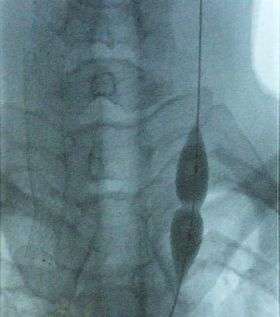

![]() Balloon dilatation of the stenosed internal jugular vein (photo from an X-ray angiograph monitor). While pressure in the balloon is relatively low, stenosis prevents the balloon from inflating in the middle. Further increase in pressure will dilate the narrowing and restore the full blood flow. | |